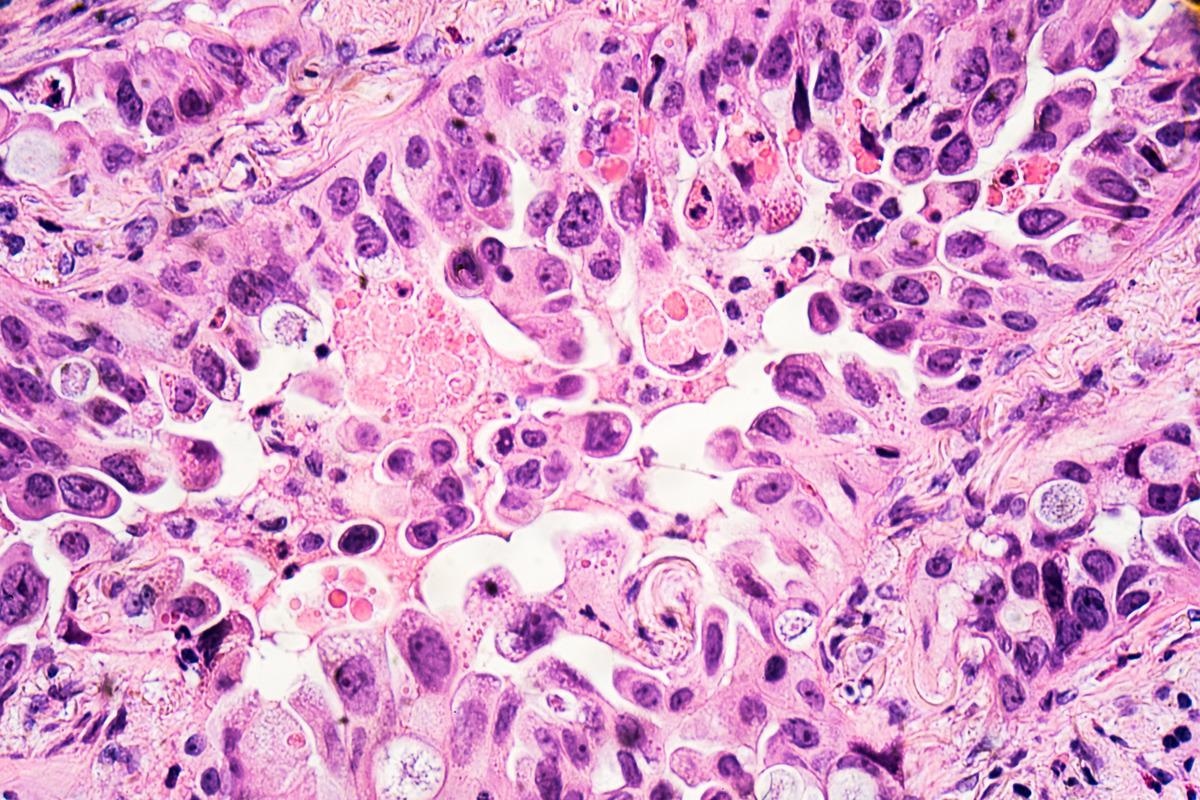

Study: The effect of COVID-19 mRNA vaccine on respiratory system: human lung carcinoma cells by means of Raman spectroscopy and imaging. Image Credit: David A Litman/ShutterstockStudy: The effect of COVID-19 mRNA vaccine on respiratory system: human lung carcinoma cells by means of Raman spectroscopy and imaging. Image Credit: David A Litman/Shutterstock